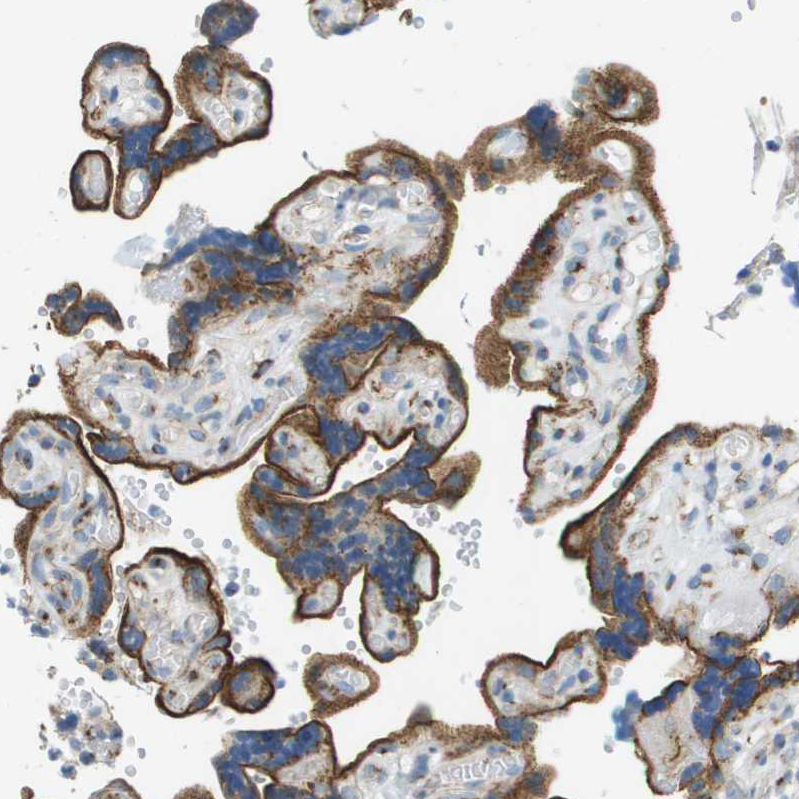

Immunohistochemical staining of human placenta shows strong granular cytoplasmic positivity in trophoblastic cells.